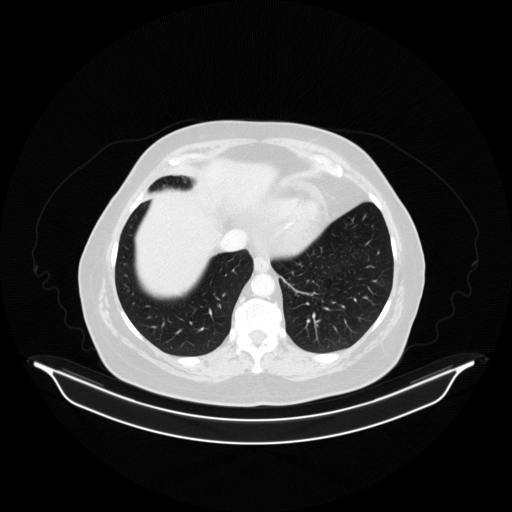

Image Grid

4Γ—3 grid: Rows show different image types (Original NATIVE, Reconstructed NATIVE, Original VENOUS, Generated VENOUS), Columns show windowing techniques (No Window, Lung Window, Mediastinum Window)

Generated VENOUS CT scan (A→B translation)

Full window (WL 1023.5, WW 4095 β†’ Low βˆ’1024, High +3071)

Actual HU range: [-1024.0, 1188.4]

Lung window (WL -600, WW 1500 β†’ Low βˆ’1350, High +150)

Actual HU range: [-1160.8, 150.0]